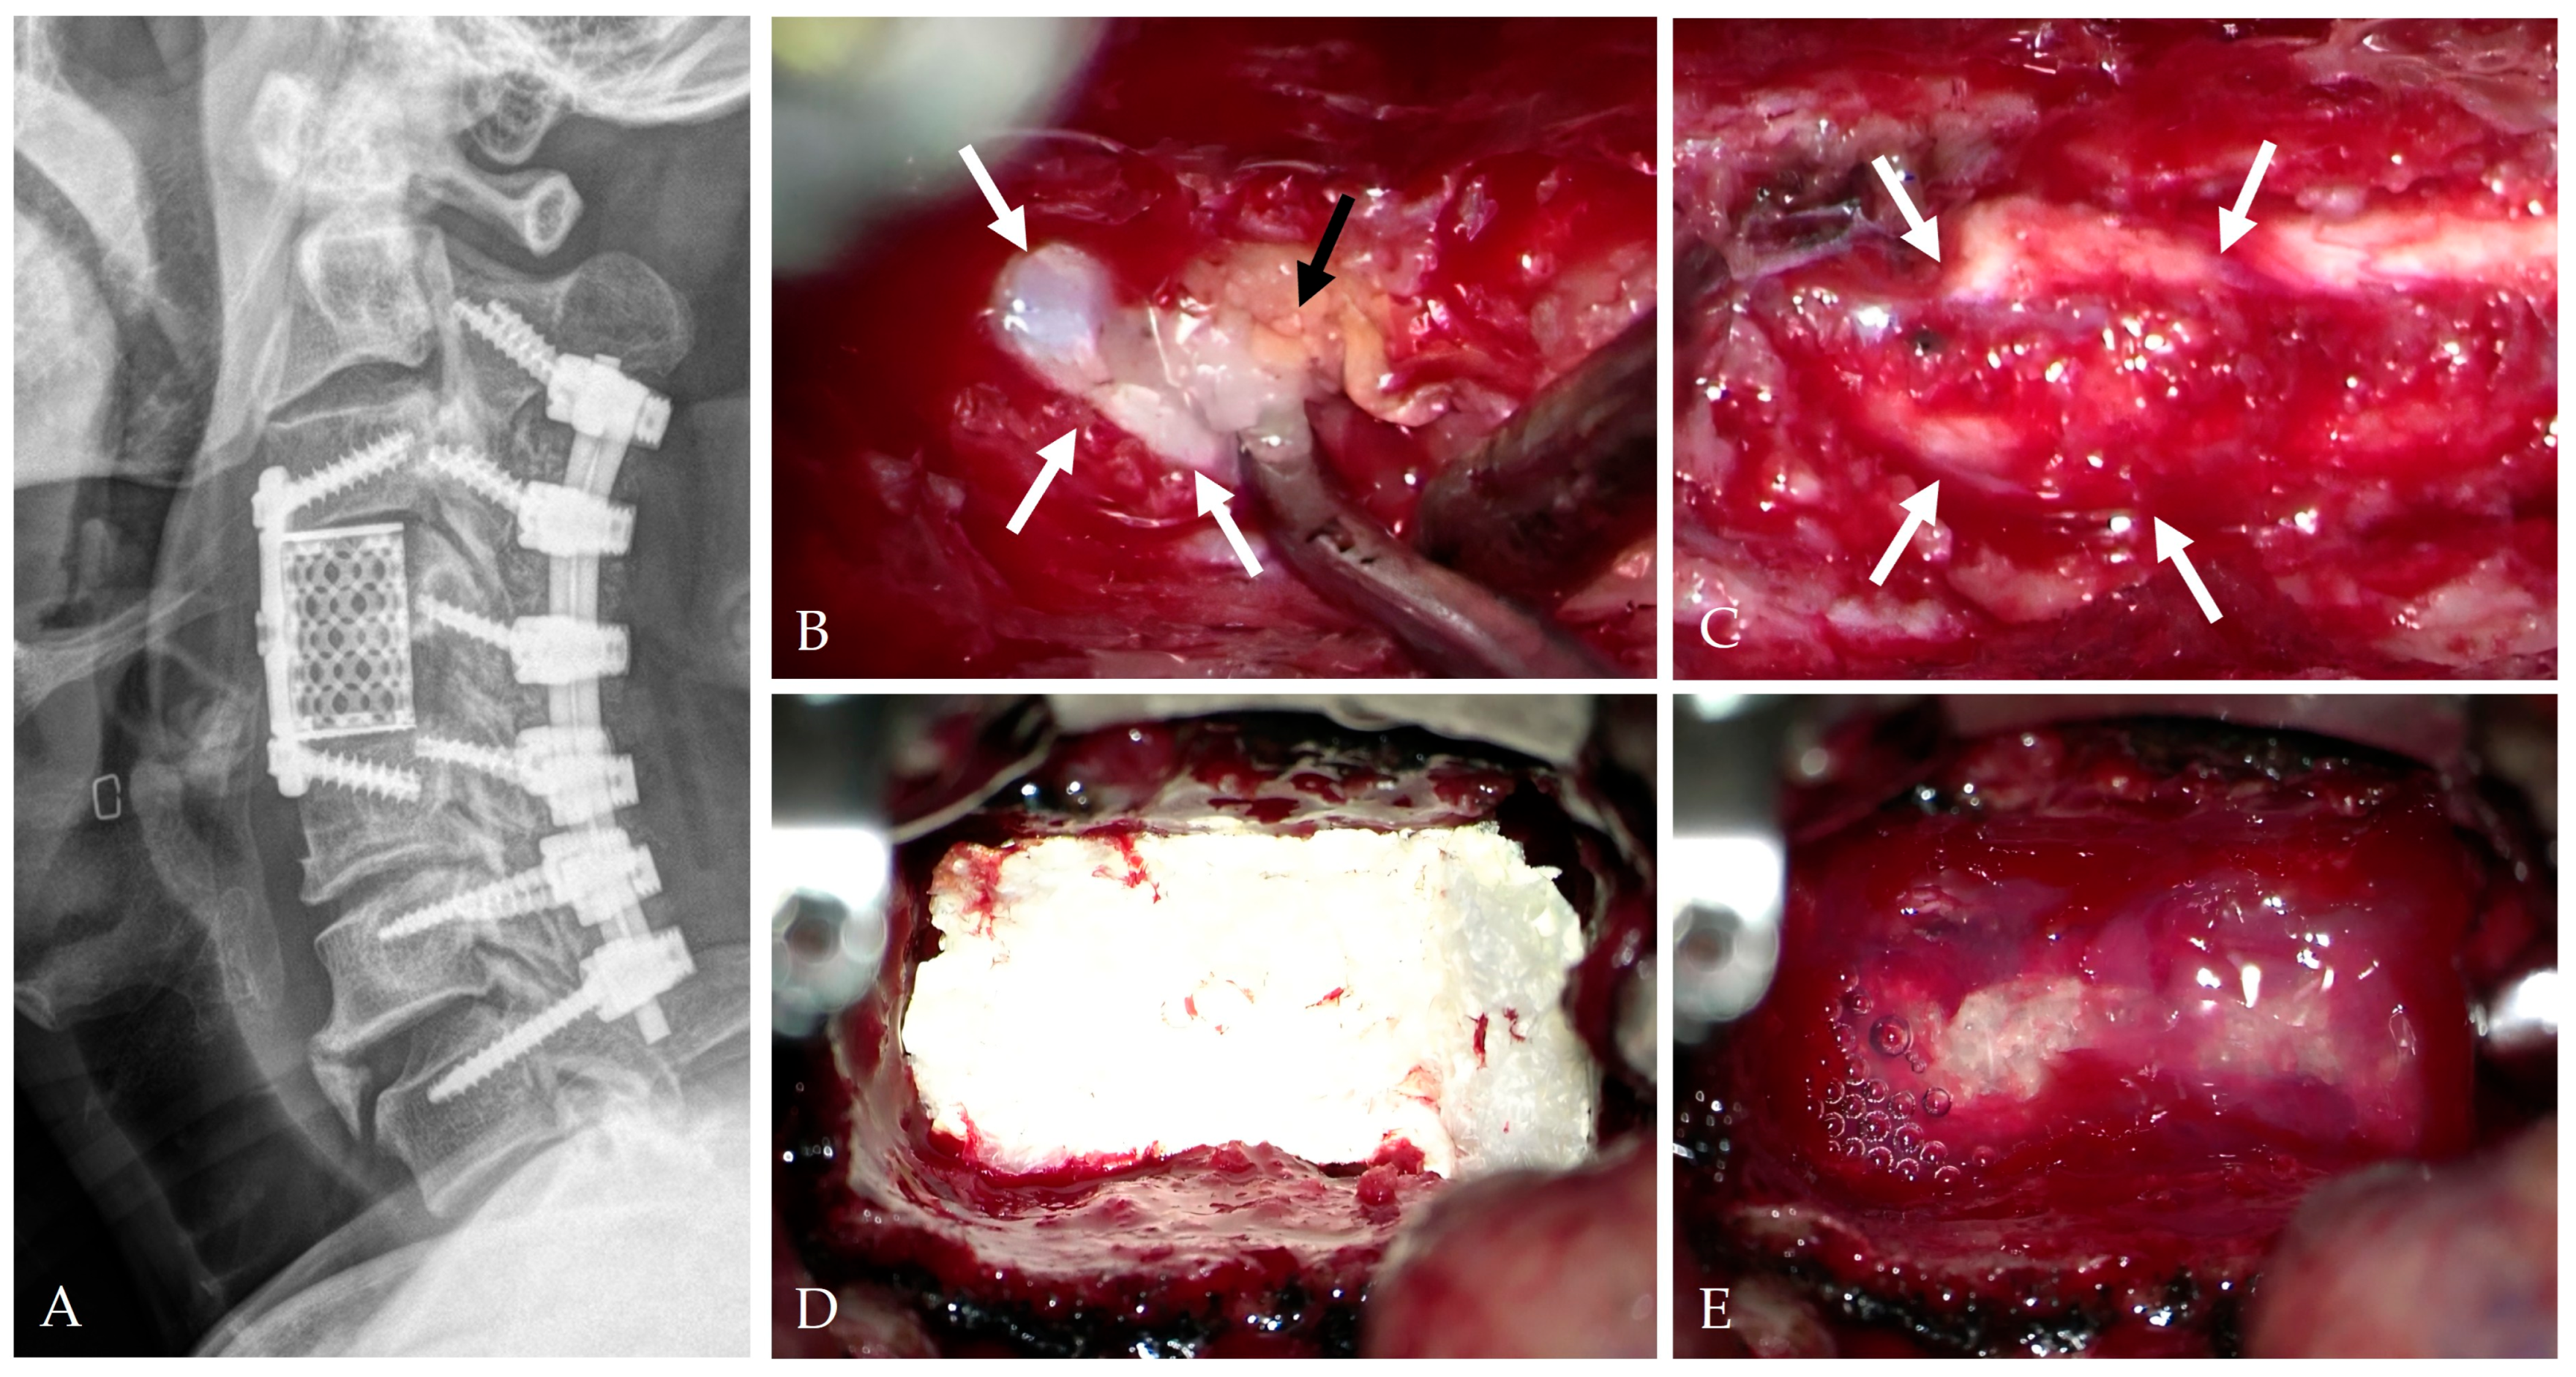

4. Intraoperative Repair Technique

4.1. Classification and Principles of Repair

4.2. Floating Repair and Dura-Preserving Techniques

4.3. Autologous Grafts and Biological Reinforcement

4.4. Artificial Dural Substitutes

4.5. Sealants and Adhesives

4.6. Composite “Sandwich” Repair

4.7. Controlled CSF Diversion

4.8. Vascularized Flap Reinforcement

- Mitchell, B.D.; Verla, T.; Reddy, D.; Winnegan, L.; Omeis, I. Reliable intraoperative repair nuances of CSF leak in anterior cervical spine surgery. World Neurosurg. 2016, 88, 252–259. [Google Scholar] [CrossRef]

- Moon, J.H.; Lee, S.; Chung, C.K.; Kim, C.H.; Heo, W. How to address cerebrospinal fluid leakage following ossification of the posterior longitudinal ligament surgery. J. Clin. Neurosci. 2017, 45, 172–179. [Google Scholar] [CrossRef]

- Elder, B.D.; Theodros, D.; Sankey, E.W.; Bydon, M.; Goodwin, C.R.; Wolinsky, J.P.; Sciubba, D.M.; Gokaslan, Z.L.; Bydon, A.; Witham, T.F. Management of CSF leakage during ACDF and its effect on fusion. World Neurosurg. 2016, 89, 636–640. [Google Scholar] [CrossRef]